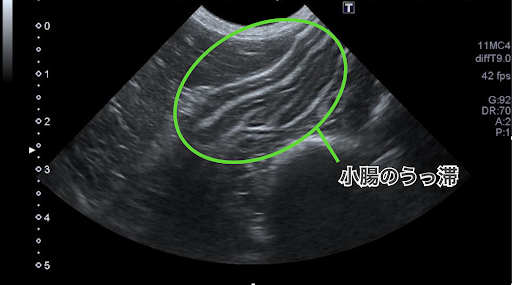

エコー検査では小腸のうっ滞が確認されました。

こちらがエコー画像です。